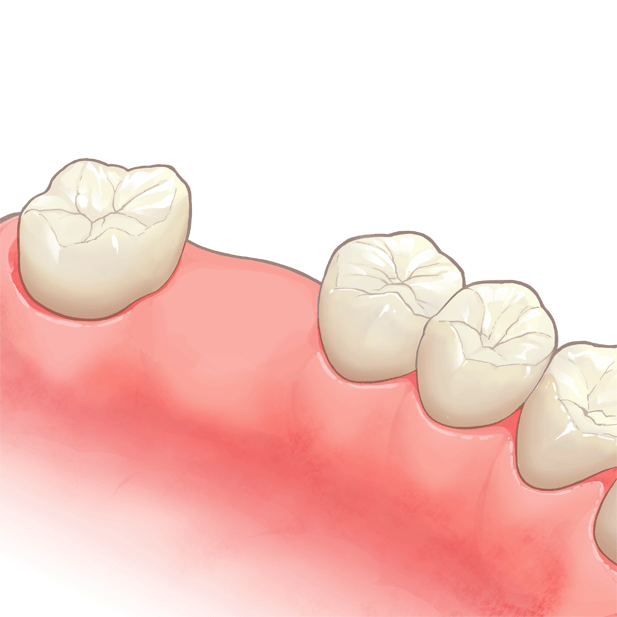

装着前